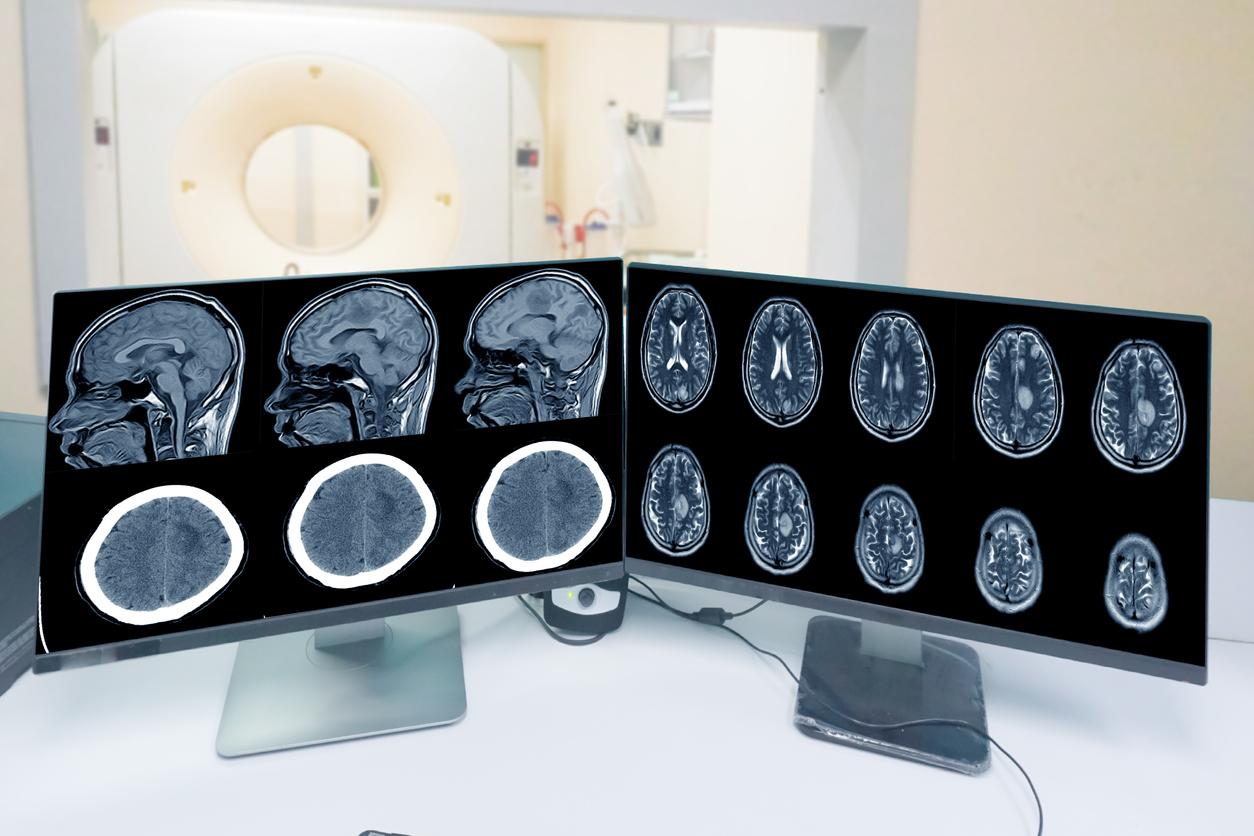

À la lumière de ces résultats, les chercheurs rappellent que la prescription d’Androcur à forte dose, en particulier pour des indications hors AMM, doit être considérée avec prudence. Ils suggèrent également qu’un "dépistage systématique et la surveillance des méningiomes par IRM cérébrale" soient proposés aux patients à qui l'on prescrit de l'acétate de cyprotérone à des doses élevées et pendant de longues périodes.